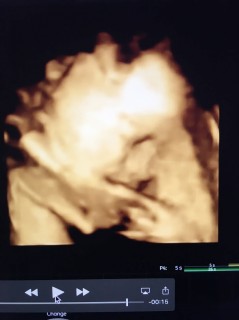

久しぶりにお顔を見せてくれました!推定体重2000gで前回から約500g増えてました!男の子確定です☆無事に会えることを楽しみにしてるよ~(^-^)

今日、検診に行って来ました! 体重は1992gだそうです! いつも4Dで顔を見る事が出来ず残念だったのですが、横顔が見れて嬉しかったです(^_^)目は線で書かれてしたいました!笑